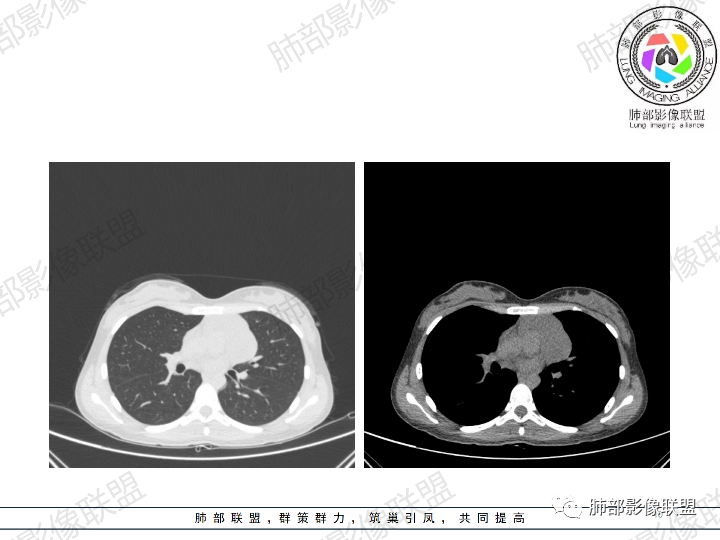

年轻女性,体检发现纵隔肿块。

影像:前纵隔一实性肿块,形态不规则,沿主动脉间隙生长,部分包绕大血管,边界欠清,周围脂肪间隙消失,平扫密度尚均匀,增强扫描大部分强化不明显,病灶左下部分似有高强化,强化病灶与血管分界清楚,考虑:1淋巴瘤(一般居中,病灶较软,包绕血管)

女性,23岁,体检发现纵隔占位。CT示前纵隔不规则占位,沿间隙生长,局部包绕大血管及心包,增强内部可见部分区域呈明显渐进性强化,其余部分强化不明显,考虑囊性畸胎瘤或神经鞘瘤>淋巴瘤,太年轻不考虑胸腺瘤

青年女性患者,体检发现左前纵隔占位性病变,胸部CT:左前纵隔见一不规则占位性病变,整体边界清楚,紧贴血管,间隙不明显,内部密度尚均匀,未见钙化及脂肪密度,增强扫描不均匀轻度强化,总体考虑偏良性病变,胸腺增生?

23岁女性

无症状

这个病灶有点怪

1、形态,似乎与常规肿瘤不一致

2、有间隔

3、密度强化有点怪

这些边缘收缩

符合胸腺正常形态

这是腺体内的一个囊性病变:

这是腺体内的另一个

倾向于:一个正常增大的腺体内的病变

根据部位:腺体首先考虑胸腺,其次才考虑异位结构

胸腺内囊、实性占位

首先支持胸腺增生并感染

其次胸腺瘤

然后才考虑异位的病变

这个病例的特点就是病灶整体符合胸腺的形态,如果它是肿瘤,它周围侵袭性不明确的话,它应该膨隆的挺厉害,它单纯就是一个膨隆性生长的,那么它就应该是类圆形的,边缘应该是膨大的,但是这个病例不是,有些地方边缘是收缩的,那么就是原有的胸腺基础上内部出了问题,里面强化增生明显就有可能是在原有胸腺基础上里面滋生出来一个病变。年龄确实年轻,又是女性。胸腺里面的病例多是胸腺瘤、胸腺癌、淋巴瘤。既然定的是胸腺里面的病变,那么就在这里面考虑。淋巴瘤首先不是。那么就是胸腺瘤和胸腺增生,胸腺囊肿的说法也有很多,因为胸腺增生里面有一种就是囊性的增生,里面有些地方有强化,囊肿合并感染了可以有,慢性炎性的肉芽肿的可以有强化。不能排除胸腺瘤,胸腺瘤放后面,一个原因就是太年轻了。如果考虑胸腺瘤,年龄不太符合,心里不踏实。我认为大家不考虑胸腺瘤是正常的思维,写报告也是待排,放第一诊断不合适。考虑有胸腺瘤是因为强化,占位效应,间隔。